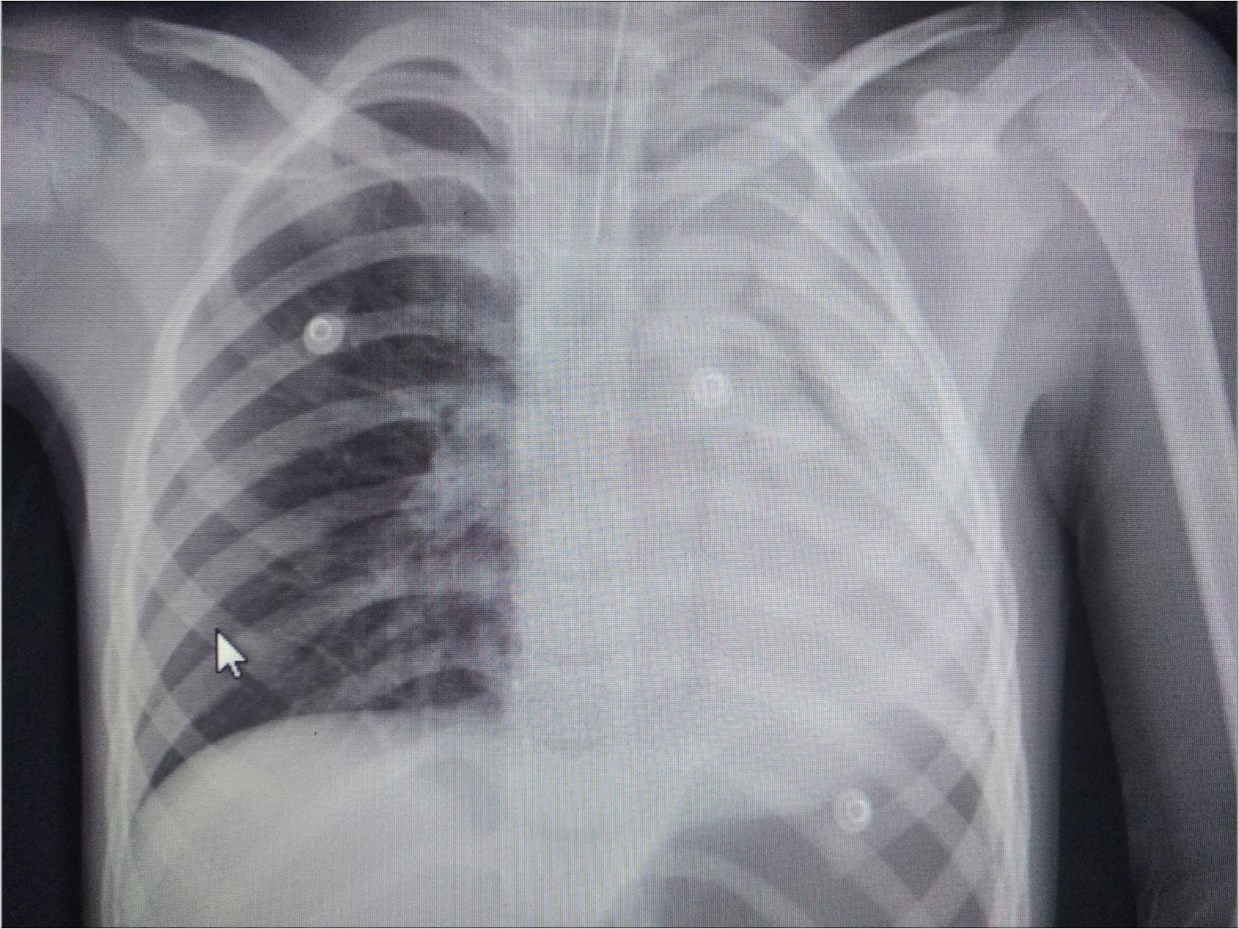

A 6 year-old boy was admitted to our hospital with the symptoms of upper respiratory tract infection (URI). He had hemoptysis 2 days prior to admission to hospital. On admission he had respiratory distress, fever (39°). Plain chest graphy demonstrated a complete opacification of the left lung (Figure 1). Thorax ultrasonography was normal and high resolution computed tomography (HRCT) of the chest revealed a 50-60% narrowing of the left main stem bronchus starting from carina downwards (Figure 2). Although there was no history of foreign object aspiration an emergent bronchoscopy was performed for a possible unnoticed aspirated foreign body. A bronchial cast located at the carineal bifurcation of trachea measuring 3x1 cm was detected and easily removed with forceps during bronchoscopy (Figure 3). The material was whitish, rubbery in consistency. Histopathologic examination of the cast revealed that it consisted of condensed fibrin, neutrophils and eosinophils. Culture was also obtained from the specimen for a possible bacterial growth. Following bronchoscopy the patient required mechanical ventilation for ventilatory support in the mode of high frequency oscillatory ventilation (HFOV) with supplementery oxygen in intensive care unit (ICU). In his 3rd hospital day, control chest graphy of the child showed complete opacification of the left lung and for a chance of residual cast in the tracheobroncial tree a repeat bronchoscopy was performed. Two seperate casts from the left main stem bronchus measuring 1.5x1 cm and 2x1 cm in length were removed with forceps and lavage with aspiration of both right and left main stem bronchus was performed. Following second bronchoscopy the transcutaneous oxygen saturation increased from 77 to 99 and control chest roentgenogram showed equal expension of both lungs. While in his stay in ICU, in addition to mediacal treatment, respiratory physiotherapy was performed regularly. He was medically treated with aerosolized dexamethasone with adrenalin. Bacterial test obtained from cast was found positive for Streptococcus viridans and vancomycin was started. On his 5th day in ICU, his respiratory status worsened and a chest graphy showed a decrease in expension of the left lung and a control bronchoscopy was performed. In this third bronchoscopy trachea and both right and left main stem bronchus were found to be patent but were found to have excessive viscous secretions. Pulmonary toilet including lavage and aspiration of thick tenacious secretions was performed. On day 12 he was transferred from the ICU and 1 week later he was weaned off the ventilator. He underwent pulmonary rehabilitation. During his 3rd year of follow up he has no further episodes of respiratory distress and he is disease free.

Figure 1.Chest radiograph showing left-sided opacification.

Radiographic findings are nonspecific and include atelectasis secondary to airway obstruction, hyperinflation due to air trapping, unilateral opacification, as seen in our case, bronchiectasis and lung infiltrates. It has been reported that HRCT may allow in some cases the visualization of bronchial casts in the airways of larger caliber 19. However the gold standard in diagnosing PB is bronchoscopy which reveals the airway obstruction by BC 3.